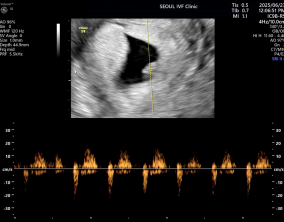

두 줄에서 심장소리까지, 따뜻하게 이어진 시간

이예흔 원장님을 비롯해 의료진과 선생님들 모두 친절하게 대해주셨고, 병원 전체 분위기도 따뜻해서 치료를 받는 동안 마음이 한결 편안했습니다. 그런 환경 덕분에 끝까지 치…